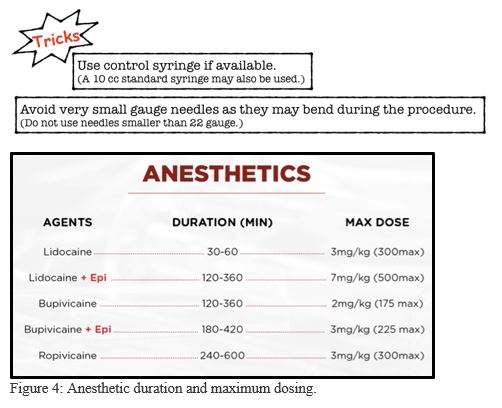

4. Gather your equipment and anesthetic

Know the duration of action and the maximum safe dose for your chosen anesthetic (Figure 4). For prolonged anesthetic duration use anesthetic with epinephrine. Inject 5-10 mL of anesthetic per nerve.